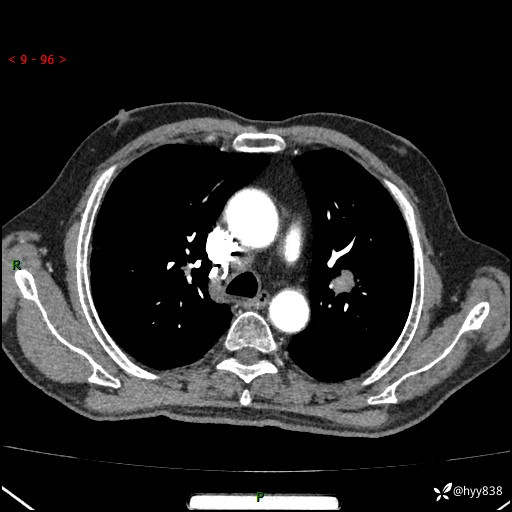

辅助检查:CT

胸部CT平扫